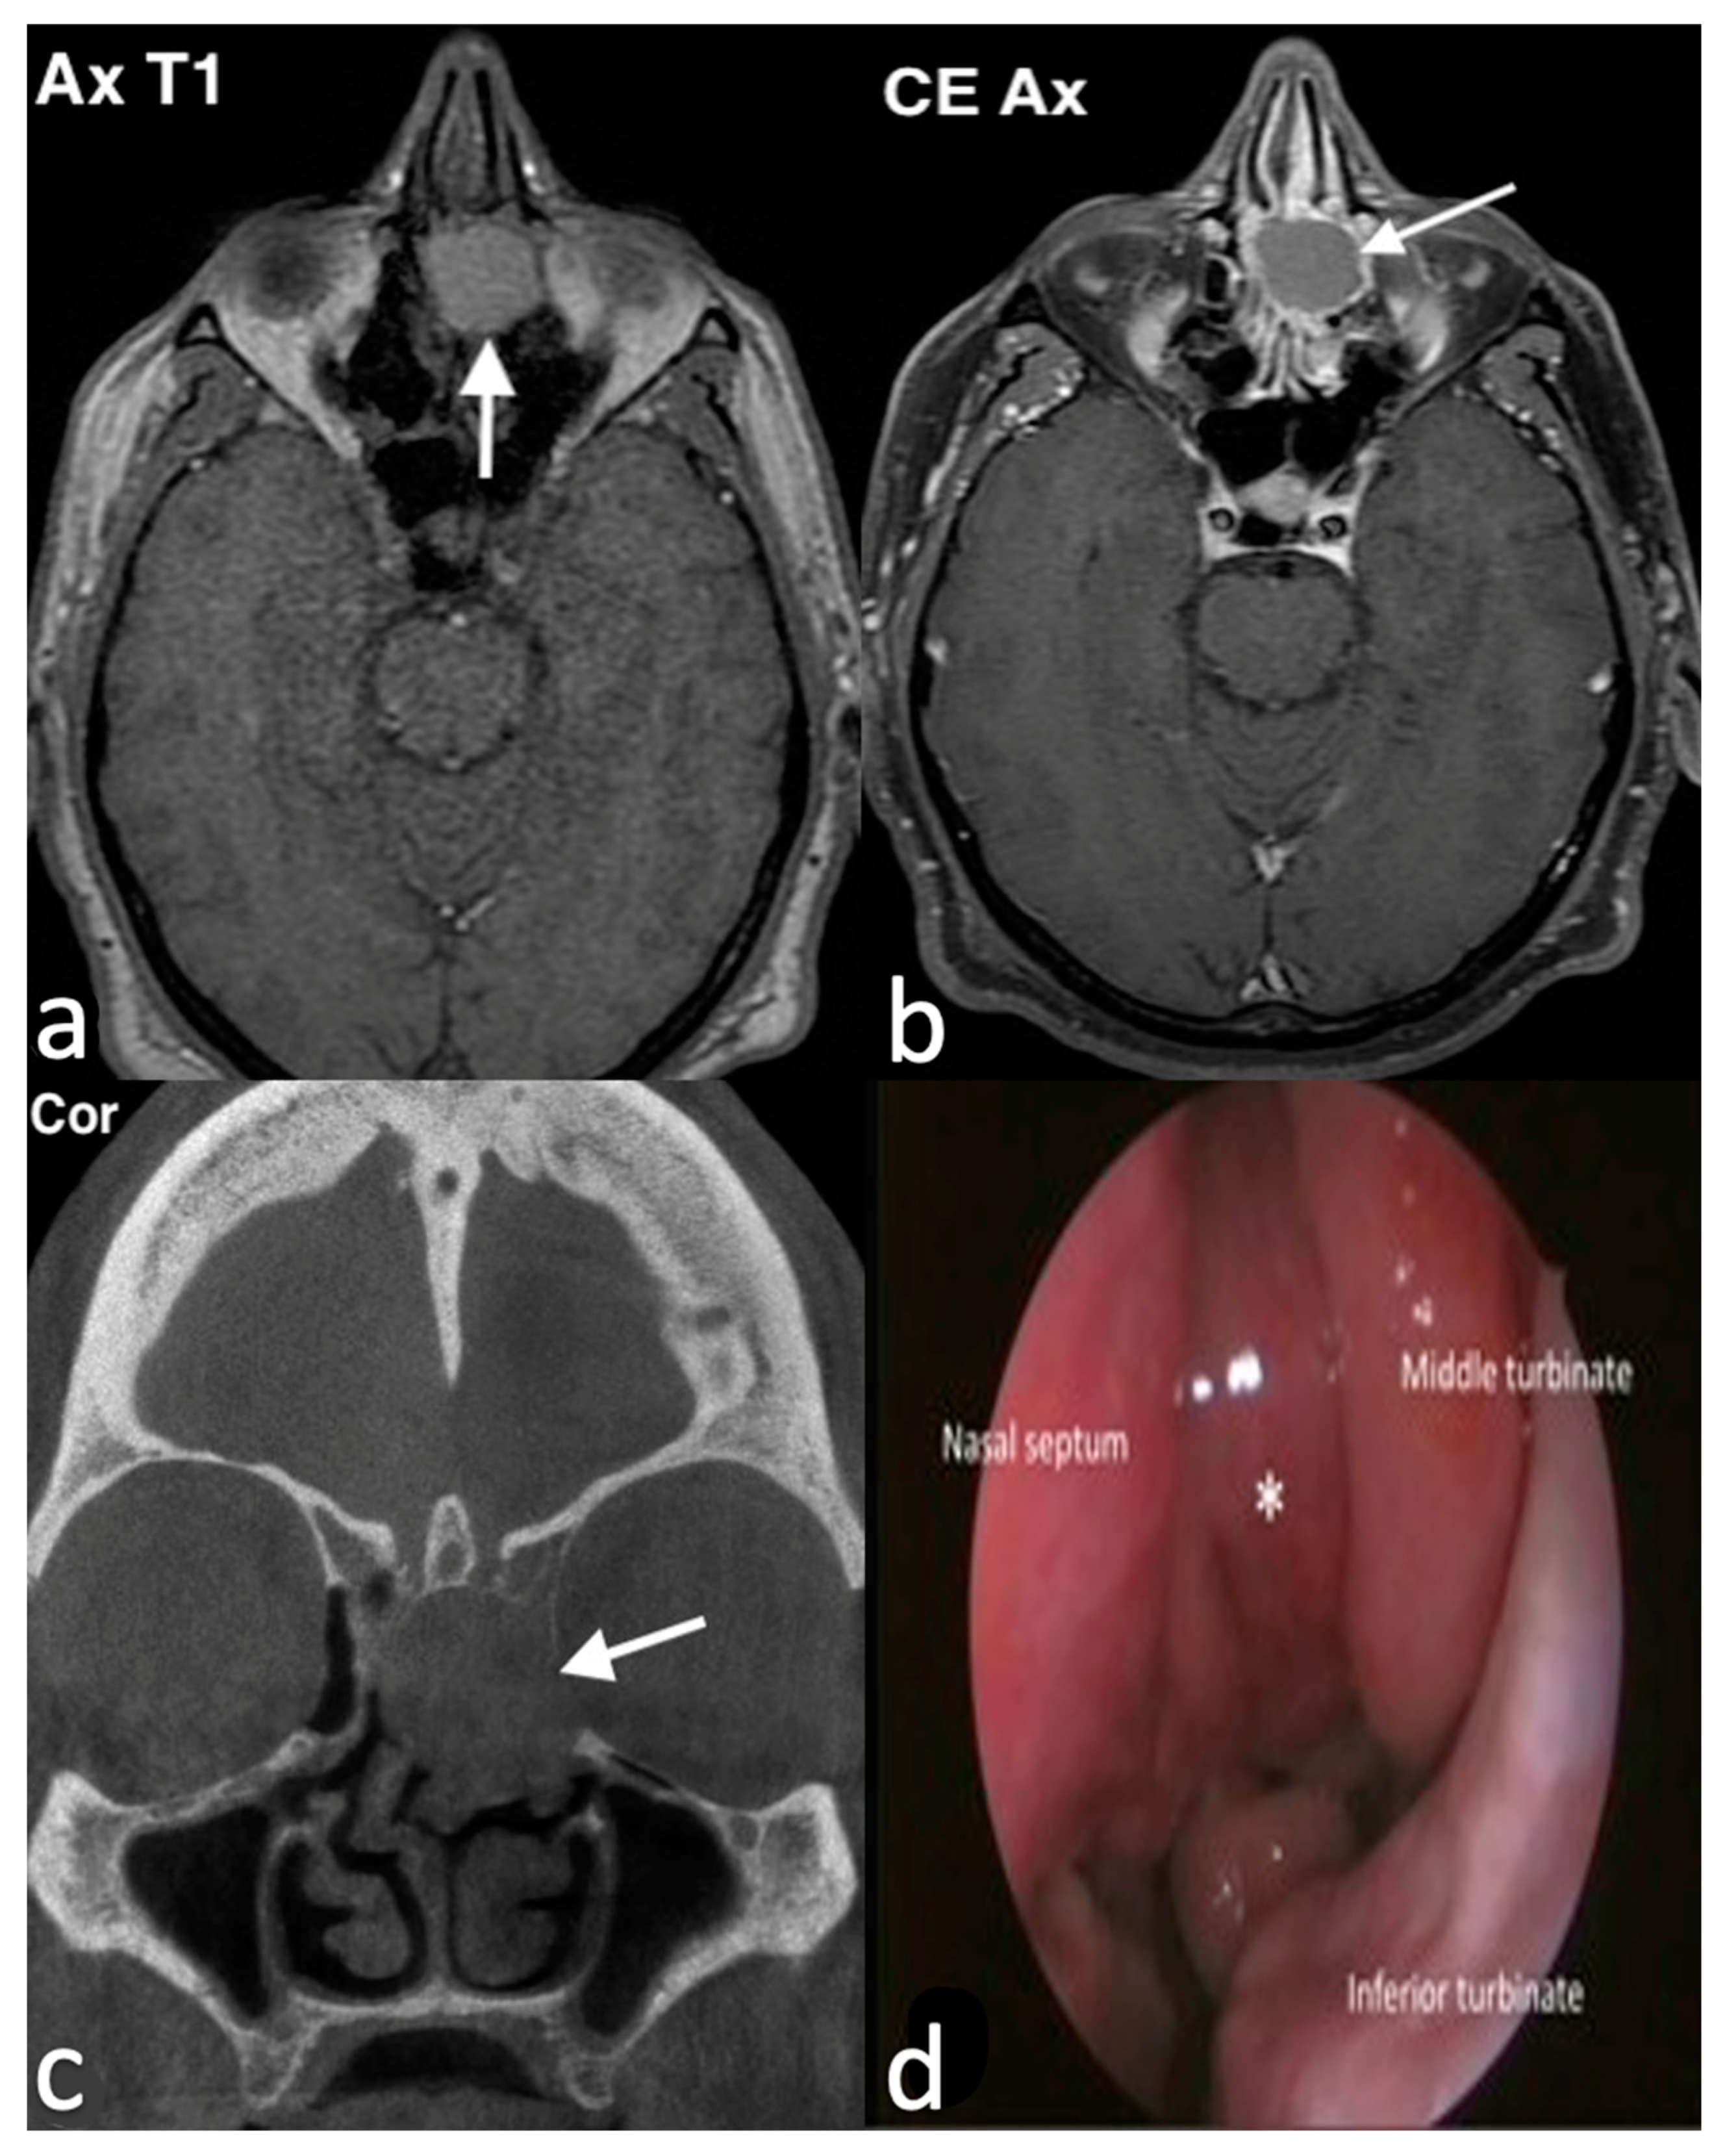

3.1.1. Septal Mucocele

3.1.2. Rinolith